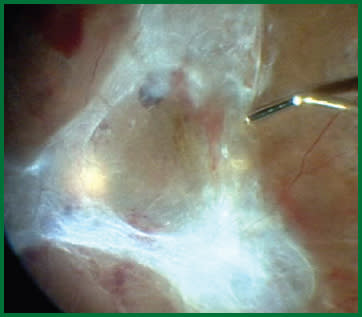

Figure 2. The 25-gauge ULTRAVIT® High Speed Vitrectomy Probe utilized as a forceps with suction only during surgery performed with the CONSTELLATION® Vision System.

The ability to modify duty cycle to control flow, independent of vacuum and cut rate, allows us to use the vitrectomy probe slowly to shave tissue without it jumping into the probe. Thick blood clots are removed quickly, and membranes can be peeled from blood vessels. The ability to manipulate cuts per minute and duty cycle also expands the utility of the vitrectomy probe. Many tasks that we would have performed with other instruments in the past can be performed with just the probe. We can get under membranes to lift and dissect them. We can use the probe as forceps, scissors or a pick (Figures 2 and 3).